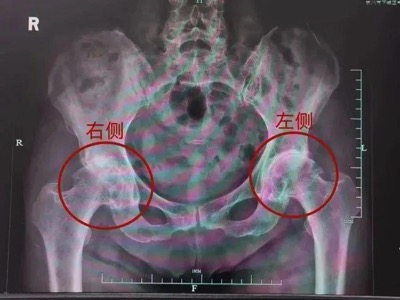

3年前盛奶奶右髋部轻微疼痛,活动时为主,卧床休息可缓解,故未予以重视未诊治。此前于别院就诊,建议手术治疗,患者拒绝。半年前,行走时右髋关节疼痛持续加重,严重影响生活。现为求进一步诊治前来我院就诊,行双髋关节影像学检查后,诊断为:右侧股骨头无菌性坏死,左髋关节骨性关节炎。